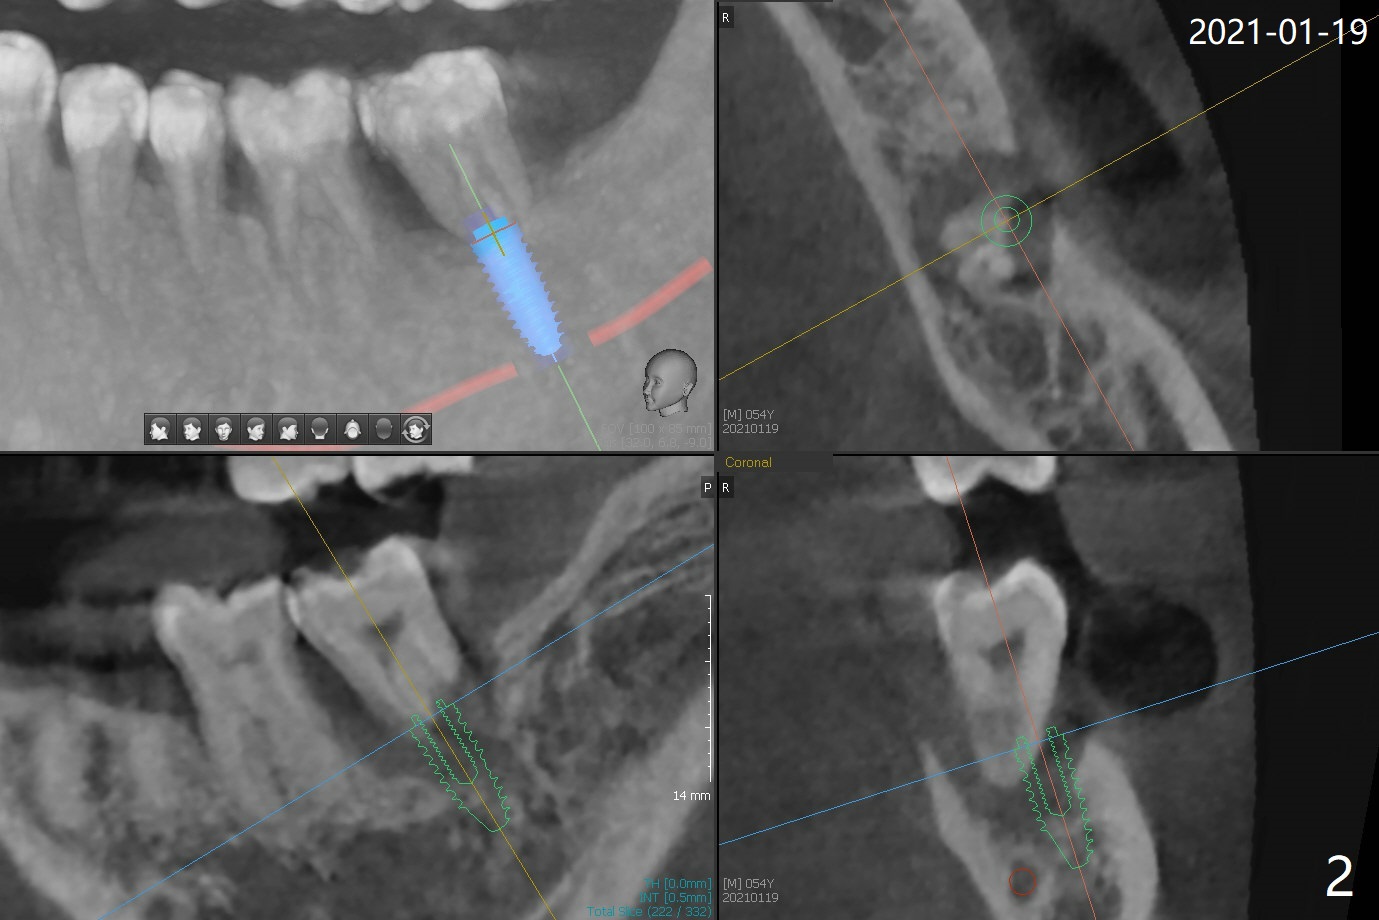

54岁男右下6,7拔除,延期种植十个月还没有完成,左下7松动(图一,二),准备即刻种植,有4-5毫米根尖骨质固定植体(图三,四),缩短治疗时间,但是必须逾越神经管,需要导板,植入偏细植体(4毫米),这样有2毫米安全地带(图四),为了减少植体过细造成植体断裂,使用五级钛植体。由于植体种得深,牙龈厚,基台袖需要长4或者5毫米(图三:粉红色),试用治疗性基台(4.5x4,4.5x15 degree A or B, 4mm),可能需要使用带角度基台(图四:蓝色),这样避免坚硬颊侧骨板,颊侧多放些粘性骨粉。第二次取模后,固定松动牙,让病人舒服些,之后必须调整咬合。